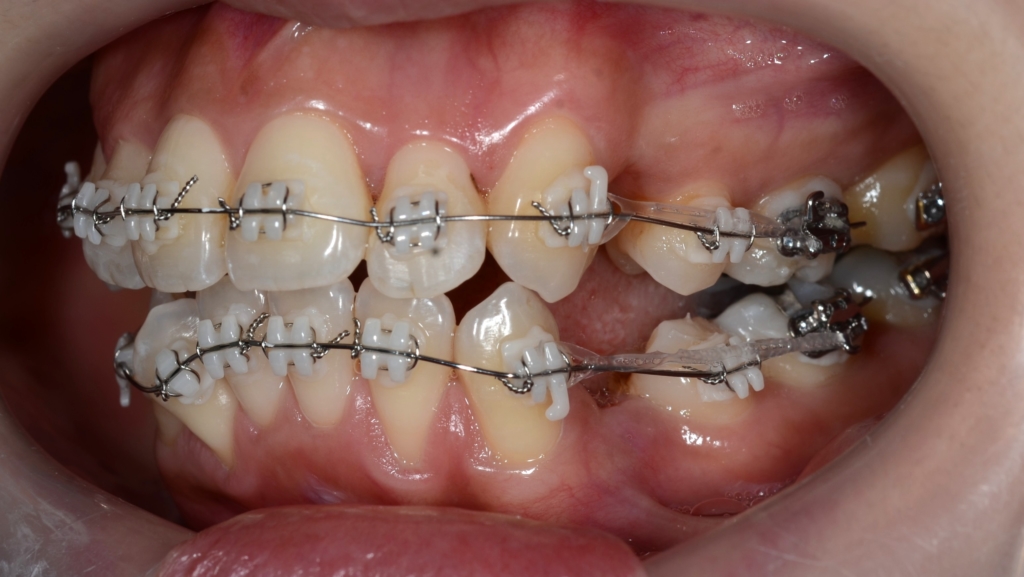

マルチブラケットシステム(スタンダード type)で矯正を開始。

上下とも前歯がきれいに並んだので、噛み合わせを考えながら前歯を引っ込めて隙間を閉鎖します。

【このステップで考えたのは・・・】

今回は、「出来るだけたくさん上の前歯を引っ込めて、下は上の歯並びに合わせる」という治療計画です。

というのも、「口元は引っ込めたいが、アンカースクリューは絶対に嫌!」という強い要望がありました。

奥歯の噛み合わせが上顎前突(いわゆる出っ歯)の噛み合わせなので、普通に前歯を引っ込めて行くと、最後に出っ歯が残ってしまいます。

本来口元を引っ込めることを狙うなら、その時点からアンカースクリューを用いて上の歯列を更に後方へ引っ込めて、口元が最大限に変化するよう頑張ります。

でも、今回は患者さんの要望でアンカースクリューが使えないので、その作戦は出来ません。

そこで、上の前歯は最大限に引っ込めるけれど、下の隙間は前歯と奥歯のお互いが動いて良い感じ(!)で無くなるように!という作戦を立てました。

そのために、2級顎間ゴムというものを、長期に渡り併用しました。

緑色の丸で囲んだ中にある「下の奥歯から上の前歯にかかる矯正用のゴム」が2級顎間ゴムです

結局、約1年8か月の間、顎間ゴムを使い続けて頑張ってもらいました。